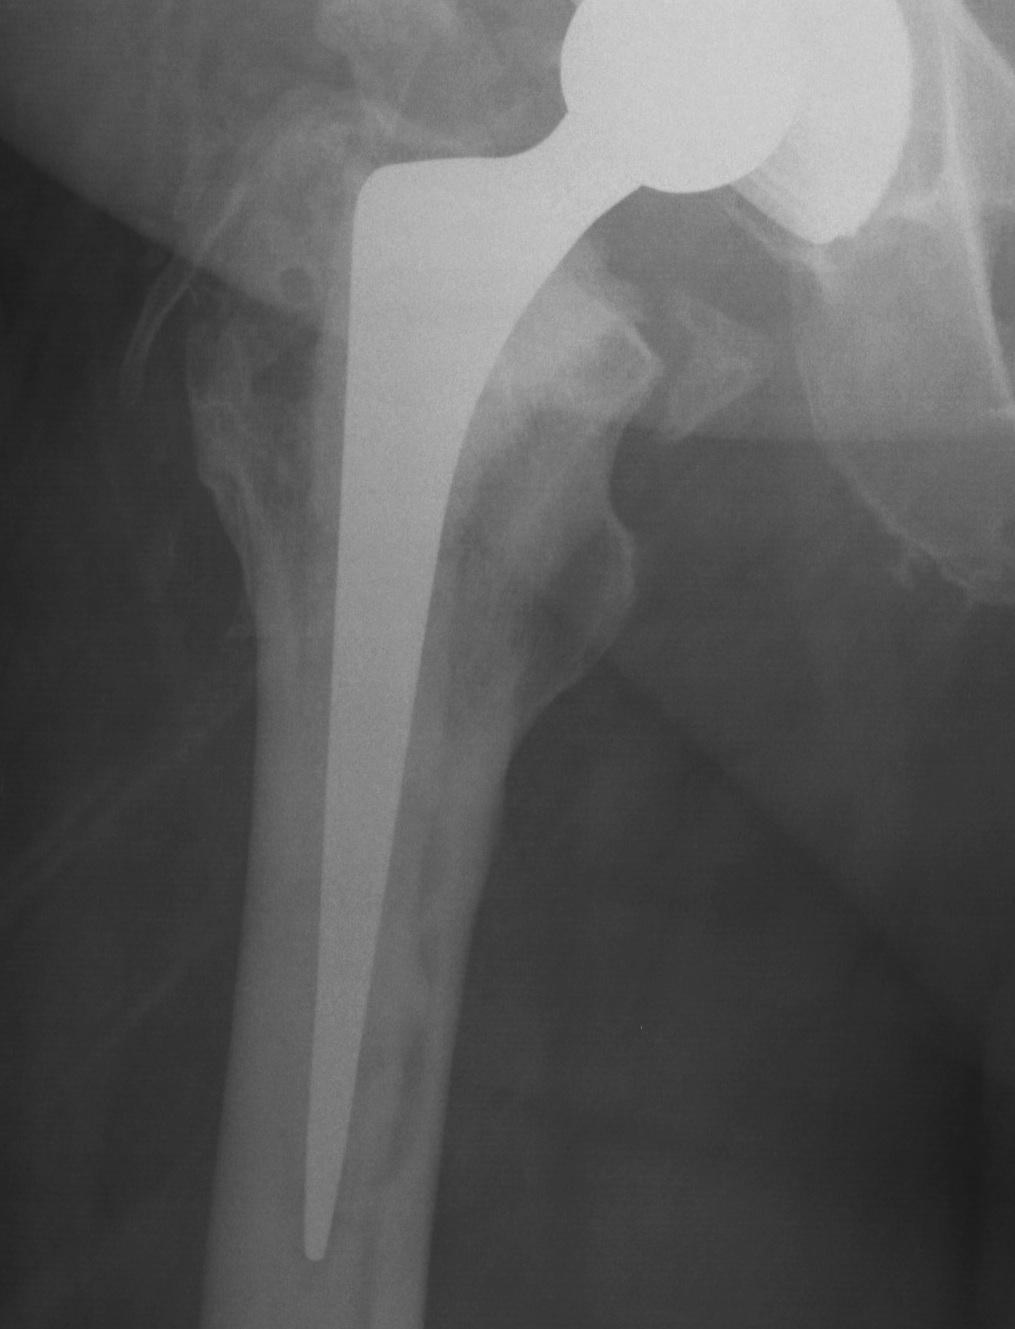

4. Impaction bone grafting

Concept

- morcellised bone graft is osteoconductive, not osteoinduction

- resorption and eventual replacement new bone

Indications

1. Uncemented distal fixation not possible (< 4cm diaphysis)

2. When reconstruction of proximal bone stock important

- young patient in whom biological solution more desirable

Prosthesis

- cemented polished collarless double tapered stem

Results

Halliday JBJS Br 2003

- 90.5% 10 year survival

Elting Clin Orthop 1995

- 93% graft incorporation

- stem subsidence in 48%

Elridge JBJS Br 1996

- > 5 mm subsidence in 22%